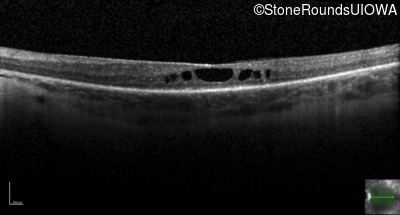

Optical Coherence Tomography - Right - 20/50

Exemplar / OCT Stack

OCT Stack